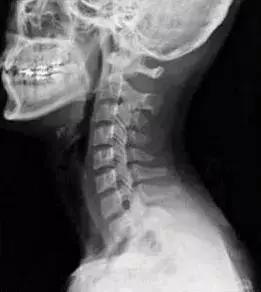

大家都知道,颈椎的正常生理曲度是前凸的,而胸椎是后凸的。在颈胸交界刚好是前凸后凸的交界,当颈椎下段过度前凸而胸椎上段过度后凸时就形成了骨性的颈胸交界骨性突起。

(正常的颈椎图)

这样的骨性突起直接影响到附着的肌肉,相关的肌肉群也会因此紧张痉挛而肿胀,两边的第一第二肋骨也因此而翻转,椎肋间的肌肉群肿胀痉挛,甚至翻转的肋骨还波及斜角肌以至于斜角肌间隙变得狭窄。这样肌肉的肿胀使得这个骨性的突起变大并且更加突出,“富贵包”就此成型。